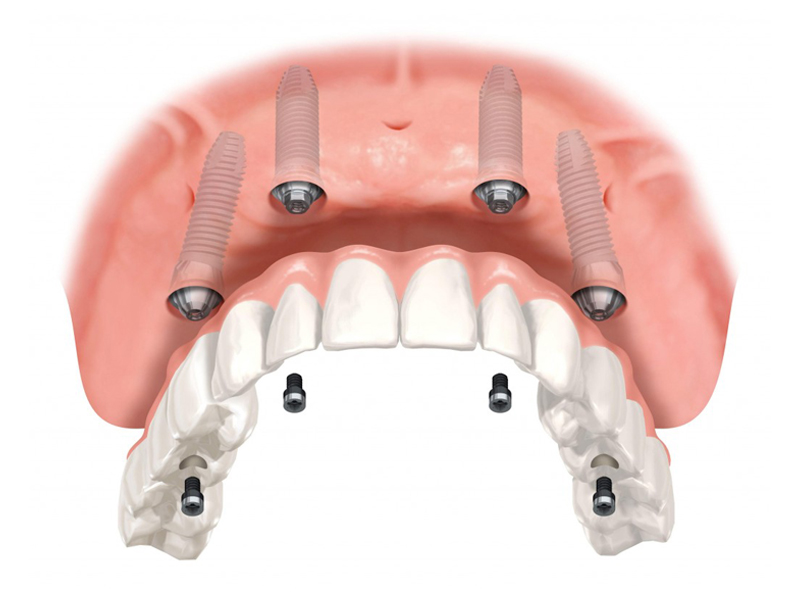

Implantology All on 4

This method is aimed both at edentulous patients who want a fixed prosthetic restoration, and at patients who have an insufficient amount of bone necessary to insert implants and are not candidates for conventional implant-prosthetic therapy.

Using the All-On – 4 method; Dental implants are inserted in the same day and in a few hours, a temporary but fixed prosthetic job is performed immediately which will remain until the implants are perfectly integrated into the bone. After about 4-6 months, definitive prosthetic rehabilitation will be performed, which will be screwed onto existing implants. The screw fixing will allow you to remove the restoration (fixed bridge) when necessary.

The specificity of this procedure is that the teeth are fixed on four implants. Thanks to the particular method of inserting the implants, bone reconstruction is not necessary, which is instead a requirement when it is necessary to reconstruct in patients who have total tooth loss.